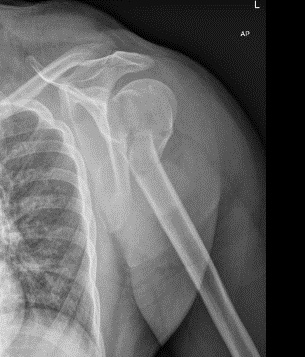

U bent onder behandeling bij Amsterdam UMC omdat u uw schouderkop heeft gebroken. Afhankelijk van het soort breuk, heeft uw traumachirurg in overleg met u besloten de breuk zonder operatie te behandelen. In deze folder krijgt u informatie over de behandeling en het herstel na een gebroken kop van de bovenarm zonder operatie.Per fase van het herstel leggen we uit welke adviezen u kunt opvolgen en welke oefeningen u kunt doen. Voor het genezingsproces is het belangrijk dat u deze instructies stap voor stap opvolgt.

Op de spoedeisende hulp heeft u een sling gekregen. U draagt deze de eerste week overdag de hele tijd, op de manier zoals u in de afbeelding hieronder kunt zien. Als u denkt dat u in bed geen bewegingen maakt met de arm, dan mag de sling in de nacht af.

De hand hangt in de sling op de hoogte van uw borstbeen en het puntje van uw elleboog hangt naar beneden. Het is heel belangrijk dat de elleboog niet ondersteund wordt, ook niet door een armleuning van een stoel of een kussen. Dit doet u om de stand van de breuk zo goed mogelijk te houden.